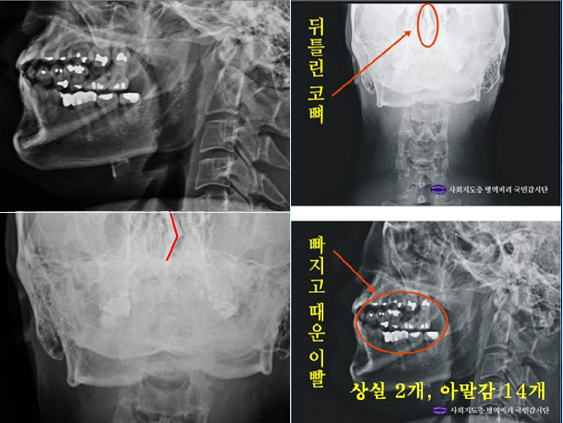

▶ 동일인의 X-Ray라면서 공군에서 찍은 것과 자생한방병원에서 찍은 것이 10곳 이상 다르다.

이번 재판과정에서 제출된, 박주신 본인의 2011년 8월 공군훈련소 X-Ray와, 박주신의 세브란스병원 MRI와 피사체가 동일한 2011년 12월 자생한방병원 X-Ray가 10곳 이상 서로 다른 것이 양승오 박사에 의해 확인되었다.

이들 X-Ray를 분석한 결과 드러난 가장 큰 차이점은 제1늑골에서 발견되는 ‘석회화 현상’이다. 이는 나이가 들어 뼈에 발생하는 퇴행성 증상의 하나로 한번 생기면 없어지지 않고 X-Ray를 통해 확인할 수 있는 것이라 한다.

◆ 자생한방병원 X-Ray에서는 오른쪽 제1늑골 부위에 ‘석회화 현상’이 나타난다. 그러나 그가 공군입대 당시 찍은 X-Ray에는 이런 모습이 전혀 보이지 않는다. 이런 차이는 두 가지 X-Ray를 찍은 사람이 동일인이 아니라는 움직일 수 없는 증거이다.

▶ 자생한방병원 X-Ray는 세브란스병원에서 찍은 X-Ray와도 다르다

▲박원순 서울시장의 아들 주신씨의 자생한방병원 엑스레이(왼쪽부터)와 공군교육사령부 엑스레이. 자생한방병원에는 늑골에 '석회화 현상'이 보이지만 공군 엑스레이에서는 발견되지 않는다. ⓒ 뉴데일리자생한방병원 X-Ray를 보면, 오른쪽 제1 늑골부위에 ‘석회화’ 현상이 나타난다. 그러나 주신씨가 공군 입대 당시 찍은 X-Ray에는 이런 모습이 전혀 보이지 않는다. 이런 차이는 위 두 X-Ray를 찍은 사람이 동일인이 아니라는 사실을 입증한다.

주신씨 구외 X-Ray 사진을 보면, 치아 상태가 매우 불량하다는 사실을 알 수 있다. 치아 2개는 아예 없고, 아말감으로 때운 치아가 무려 14개에 달한다.

치아의 치료상태는 매우 불량하고, 심지어 골반 X-Ray 사진에서는 골절된 뼈조각까지 발견됐다.주신씨의 것으로 알려진 치아 X-Ray 사진을 본 치의학 박사 C씨의 소견이다

“자료를 보면 2개의 이빨은 아예 없고, 아말감으로 때운 치아 14개가 보인다.

게다가 환자는 하악 1소구치(아래 어금니 앞쪽)까지 아말감으로 치료했다.

(젊은 사람이) 이런 경우는 매우 드물다.”“특히 전체적인 치료 상태를 보면, 소위 말하는 [야매]로 했을 가능성이 높다.

최근 국내에서 교육받은 치과의사의 치료라고 생각할 수 없을 정도다.

45번, 46번 보철 치료 및 치아 상실 문제에 있어서도 마찬가지다.

보철물로는 상당히 저렴한 비귀금속 합금을 사용한 것으로 보인다.

37번 치아는 아예 없는 상태로 방치하기도 했다.”“박주신의 가정환경을 고려하면, 이런 치료를 받았을 가능성은 1%도 안 된다.

서울 방배동에 거주했던 중산층 이상의 가정에서는 흔치 않은 상황이다.”